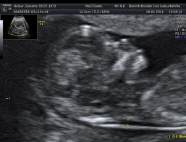

* First Trimester Screening. Messung der Nackentransparenz, Nasenbein, Combined Test (12.-14. SSW) - hier Termin vereinbaren!

2. Organscreening idealerweise in der 22.-24. SSW - hier Termin vereinbaren!